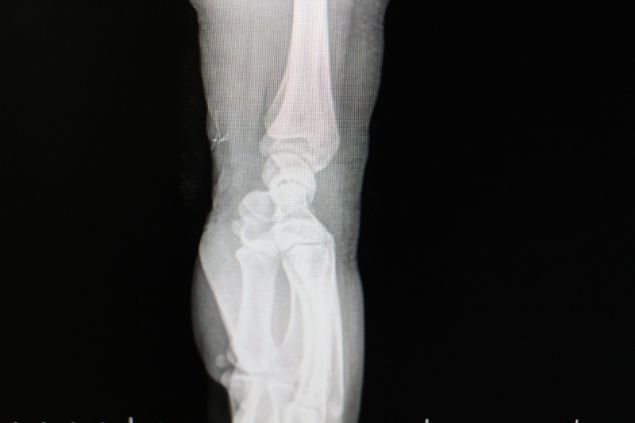

AMASYA’nın Merzifon ilçesinde vücudunda iğne şeklinde metal cisimler çıkan genç kız, aynı şoku 8 yıl sonra yeniden yaşadı.

Genç kızı hastaneye götürdüklerinde kolunda metal cisimler olduğunu öğrenmeleri üzerine şaşıran komşuları Arslan Kurkmazlı da, “Duyan herkes hayret ediyor. ‘Öyle bir şey olur mu?’ diyorlar. Normal iğne ama ucu, dibi yok” diye konuştu.

Doktorlar ameliyatla iğneleri almıştı. Aradan 8 yıl geçtikten sonra kolumda morluklar oldu. Doktora gittik. ‘Ezilme var’ dedi. Bir ay sargıda kaldı. Ağrılar sürünce iğne olduğu anlaşıldı” dedi.

MUHTEMELEN METABOLİK BİR HASTALIK: Ortopedi servisine başvuran Sevda Topkök’ün çekilen röntgen görüntülerinde kolunda cisimlere rastlandığını doğrulayıp hastalarını üniversite hastanesindeki uzmanlara yönlendireceklerine değinen Merzifon Kara Mustafa Paşa Devlet Hastanesi Başhekimi Uzman Doktor Selçuk Sezikli de “Bu nadir görülen bir durum.

Vücutta muhtemelen metabolik bir hastalık araştırması gerekebilir” şeklinde konuştu.

Sol bacağında kaşıntılara yol açan kızarıklığın tedavisi için gittiği İstanbul’da doktorların ayağında çok sayıda metal iğne şeklinde cisimlerin olduğunu söylemesi üzerine şok yaşayan Sevda Topkök, ameliyatın ardından memleketine döndü. Yaşadıklarını tam unutmak üzereyken benzer kızarıklıkları bu defa 8 yıl sonra sol kolunda gözlemleyen genç kızın başvurduğu Merzifon Kara Mustafa Paşa Devlet Hastanesinde çekilen röntgeninde iğne şeklindeki metal cisimlere rastlandı.

Bileğindeki 4 cismin çıkartılması için il merkezine de yönlendirildikten sonra kolunda 4 cisim daha saptanan 24 yaşındaki Topkök, “8 yıl önce bacağımdan 35 tane iğne çıktı.